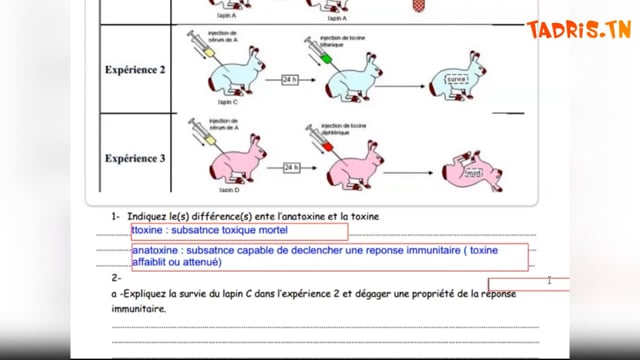

Sciences SVT